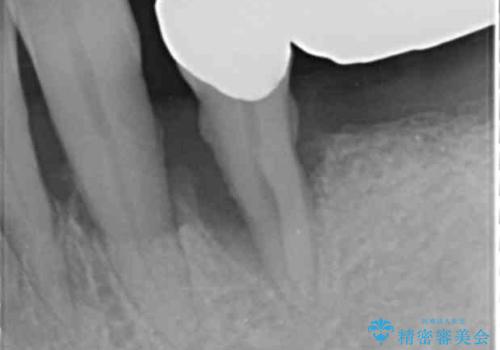

精査したところ、全顎的な重度の歯周病により下顎前歯に激しい動揺を認めました。

再生療法から1年後リエントリー手術により骨の再生を確認し、骨外科処置(骨を平らにして歯周ポケットの根本的な改善を図る処置)を行ったのち、連結補綴を行いました。

骨吸収と動揺が著しい前歯1本(左下1)のみ抜歯しております。